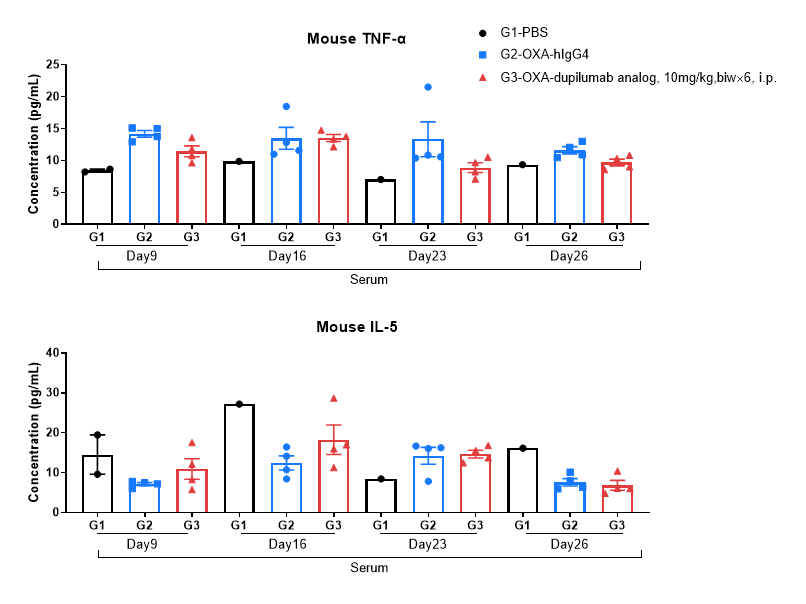

Protein expression analysis in OXA-induced AD model of B-hIL4/hIL4RA mice by MSD.

Ear and skin samples of modeling area were collected from at day 9, 16, 26 and 26 and analyzed by Luminex. Tissue sample homogenate supernatants were loaded for detection.